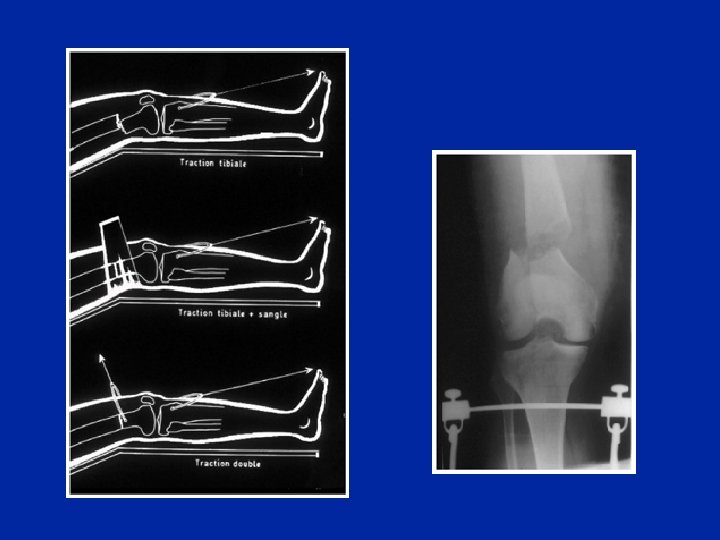

Fratture in iper-estensione scomposte n Trazione assiale delicata sul ginocchio flessi fino a che l’operatore « riposiziona » l’epifisi verso il basso ed indietro n Eventuale correzione della traslzione laterale